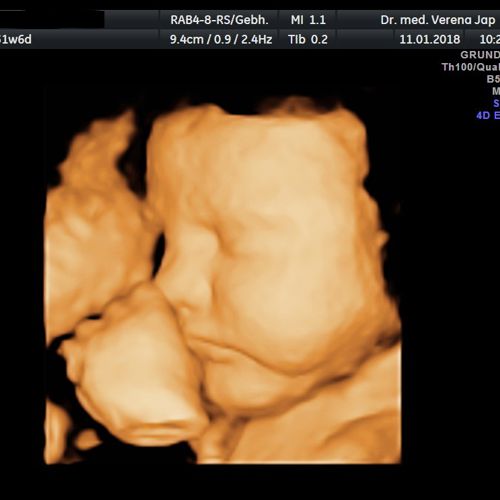

Hier wollen wir Ihnen einen Einblick in die Praxisräumlichkeiten geben. Die Untersuchung findet in ruhiger Atmosphäre in einem hellen und freundlichen Raum statt. Gleichzeitig bieten wir Ihnen eine moderne und zeitgemäße Ausstattung mit Ultraschall auf höchstem technischen Niveau, Phasenkontrastmikroskopie und Videokolposkopie.